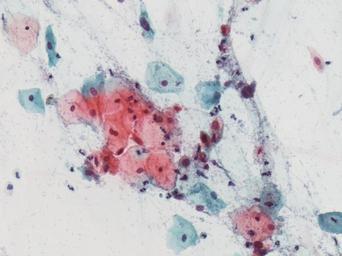

Keywords: lesión intraepitelial escamosa de bajo grado lesiónintraepitelialescamosadebajogrado citología de cuello uterino citologíadecuellouterino citología exfoliativa ginecológica citologíaexfoliativaginecológica citología de cribado citologíadecribado citología anatomía patológica anatomíapatológica bethesda 2001 bethesda2001 osuna cérvix uterino cérvixuterino hpv españa screening lsil enfermedades de transmisión sexual enfermedadesdetransmisiónsexual imágenes de citología ginecológica imágenesdecitologíaginecológica papanicolaou test de papanicolaou testdepapanicolaou tinción de papanicolaou tincióndepapanicolaou drawing Células con núcleo y citoplasma aumentado de tamaño, núcleos irregulares, como plumosos, tendencia al color naranja de muchas células, halos en algunos casos, núcleos dobles en otros, algunos núcleos hipercromáticos. Células con núcleo y citoplasma aumentado de tamaño, núcleos irregulares, como plumosos, tendencia al color naranja de muchas células, halos en algunos casos, núcleos dobles en otros, algunos núcleos hipercromáticos. |